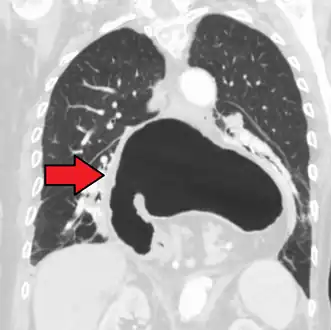

A large hiatal hernia as seen on CT imaging

A large hiatal hernia as seen on CT imaging- As seen on ultrasound[9]